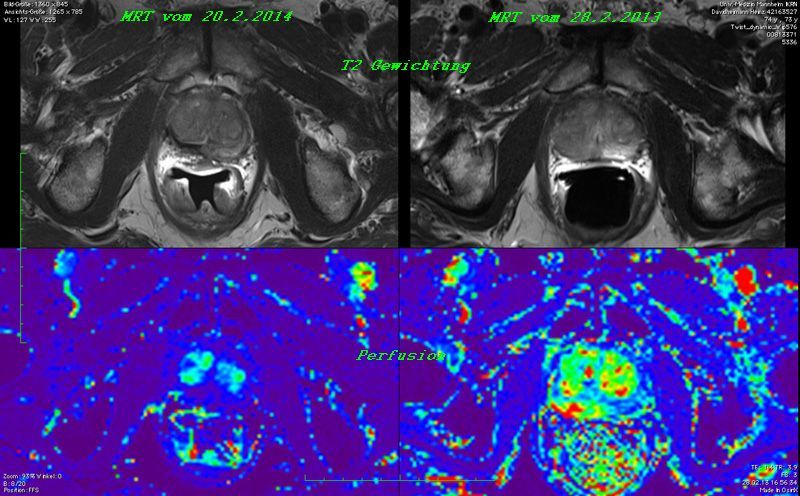

20.2.2014 erneutes mpMRT bei Prof. Schönberg, Mannheim.:

Ergebnis:

Das Prostatavolumen von 69 ml ist auf 35 ml reduziert und der Tumor von 2,9 x 1,1 cm ist nicht mehr feststellbar.

Siehe nachfolgendes Bilddokument!

Gegenüberstellung der MRT Aufnahmen

vom 20.2.2014 nach der Therapie                           vom 28.2.2013 vor der Therapie